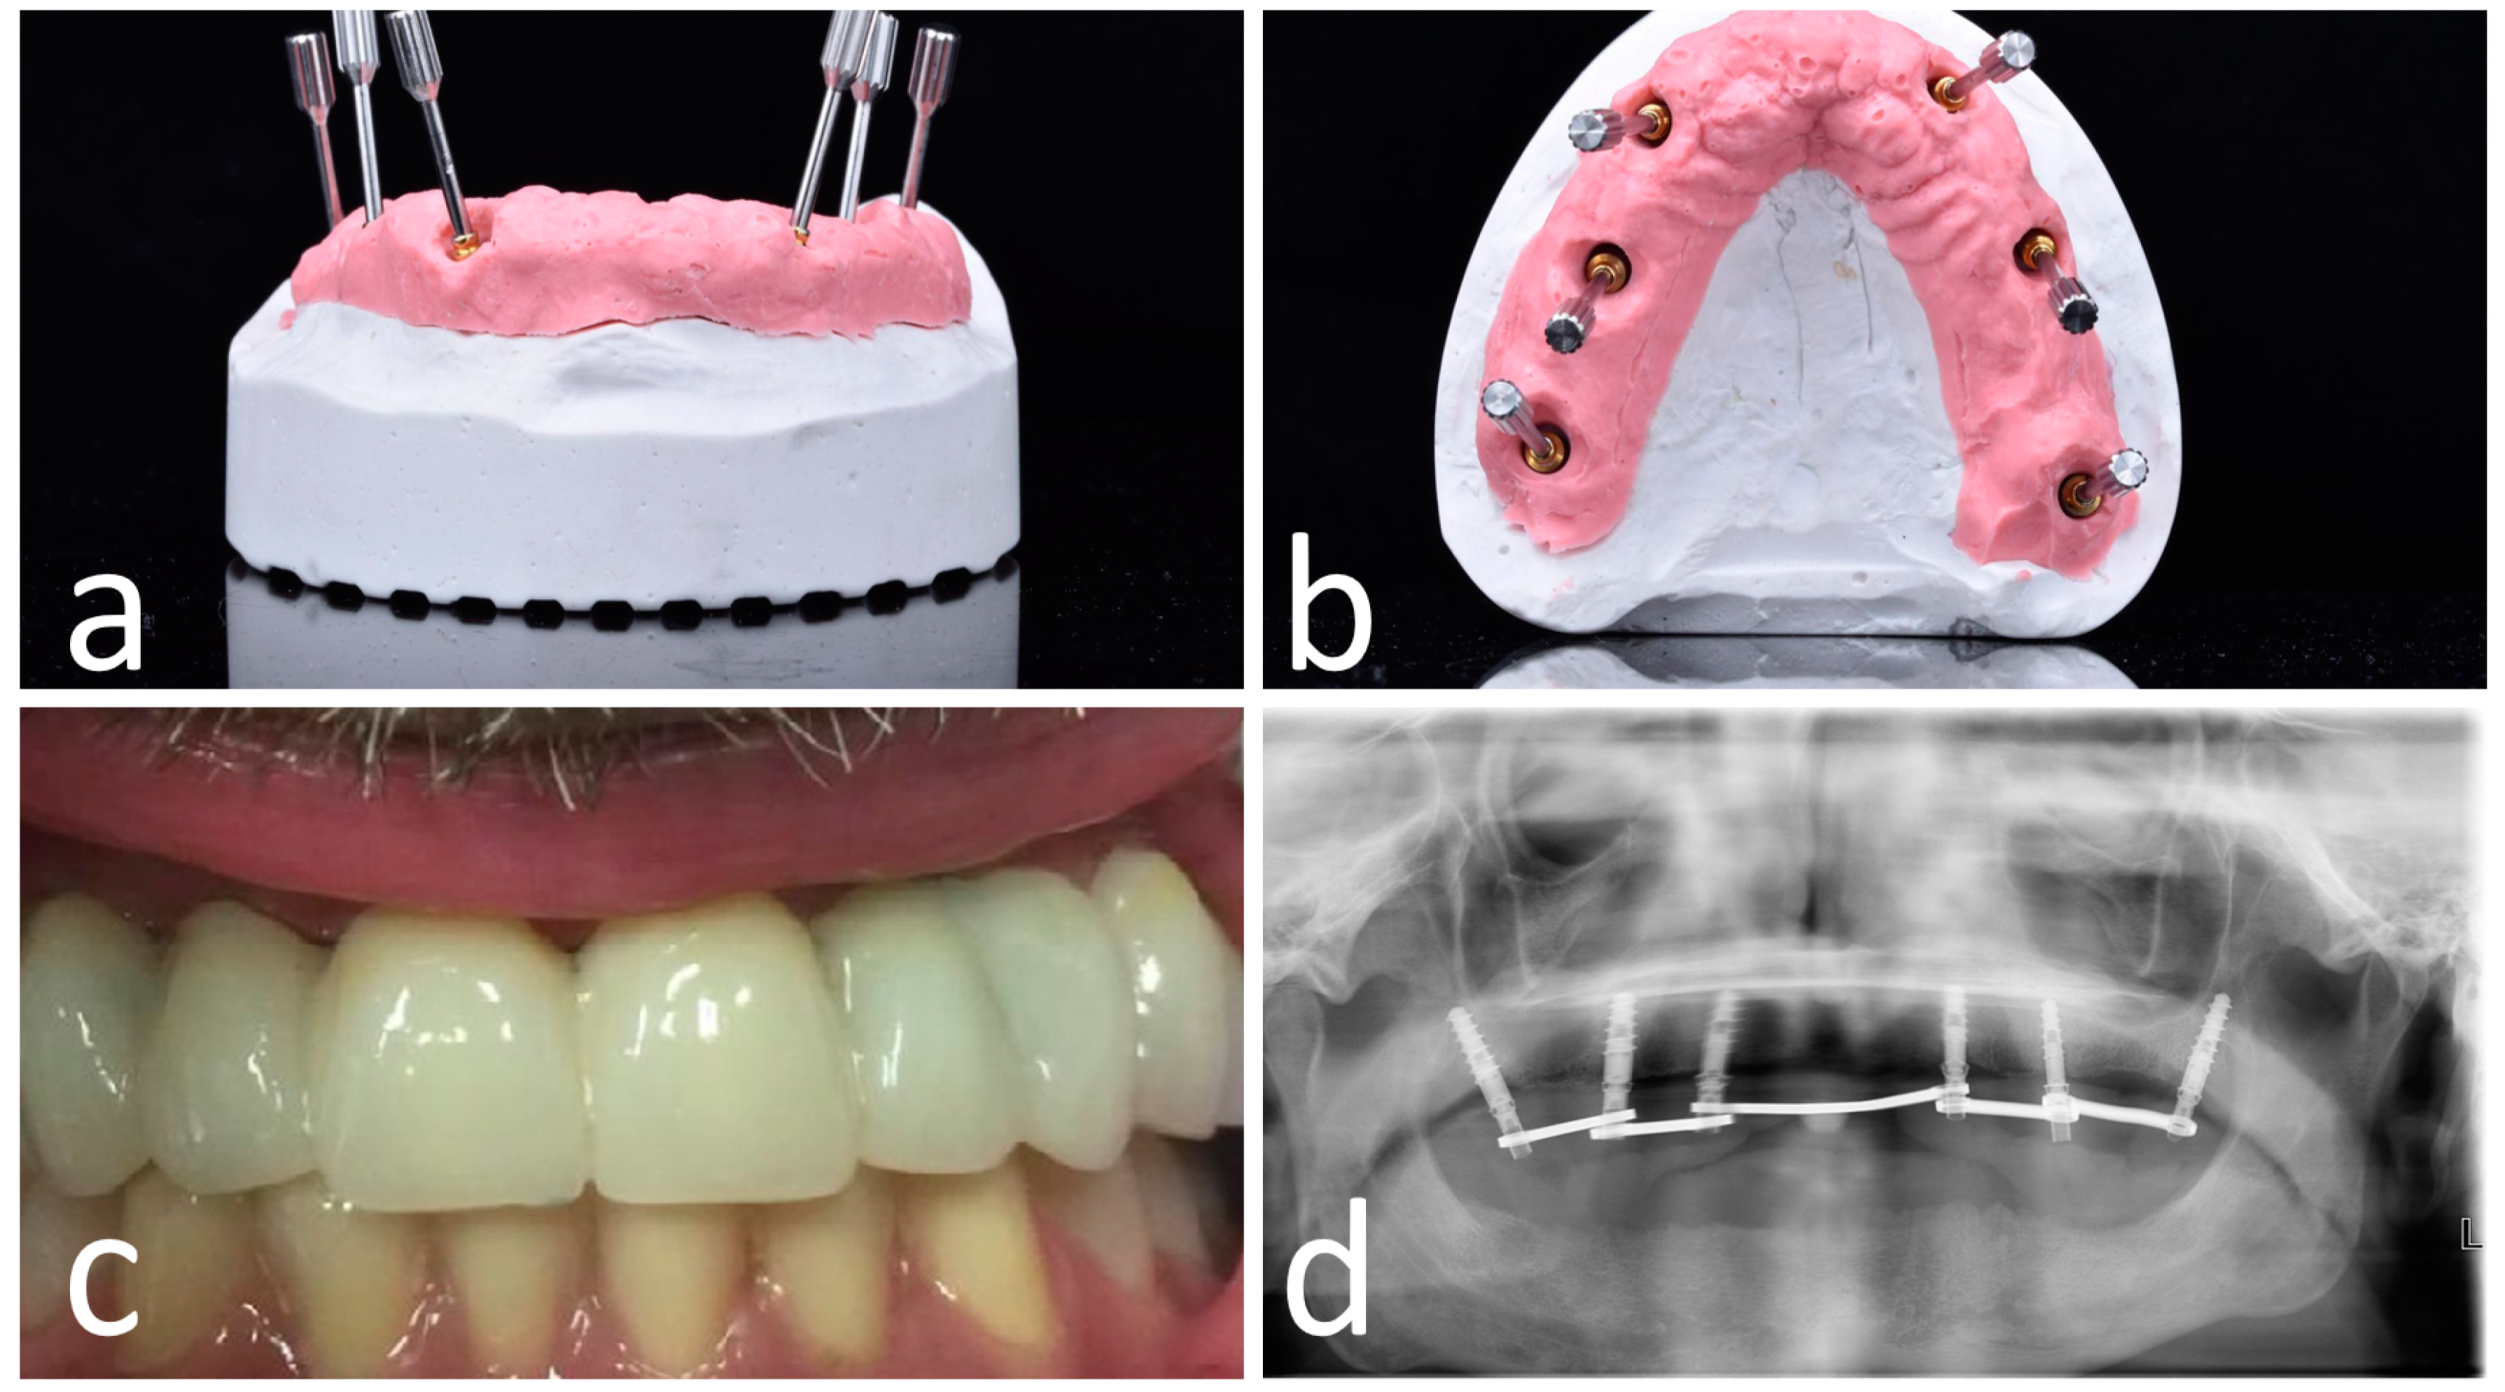

Figure 6.

OT-bridge abutments use the “Extragrade™” feature, a system allowing to compensate up to 80° of the divergence between two implants (a,b). Pictures c and d show the clinical (c) and X-ray (d) view of the provisional prosthesis using OT-bridge abutments.

Figure 7.

Opt X-ray (a) and clinical (b) view of the provisional prosthesis realized using conventional straight and angled multi-unit abutment (M.U.A.).